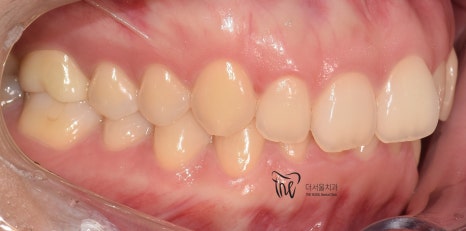

구강 내 사진을 먼저 보여드리면, 윗니가

아랫니를 깊게 물고 있어서 아랫니가 거의

눈에 띄지 않는 것을 보실 수 있습니다.

딱, 전형적 과개교합 의 양상을 보여주고 있습니다.

그러면서 치아의 중심선이 맞지 않으면서

악궁의 크기 또한 비대칭인것을 볼 수 있네요.